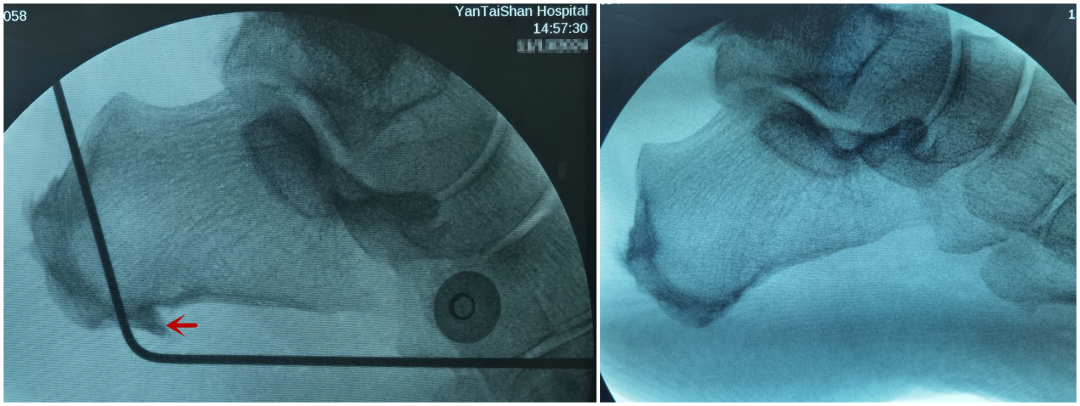

手术前后对比,左图所示为跟骨骨刺。

前段时间,他慕名来到了烟台山医院足踝外科,曲文庆主任医师团队组织病例讨论,为他量身定制了手术方案。术中,医生通过关节镜切除跟骨骨刺,清理炎性组织。手术取得了理想的效果,影响刘先生多年的疼痛得以有效消除。